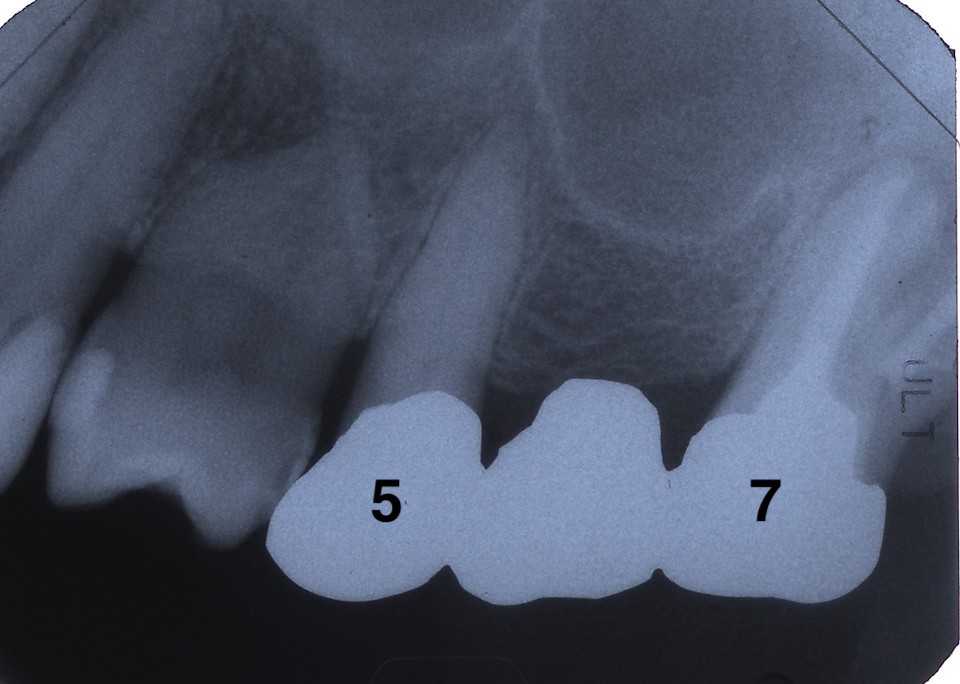

50代女性、左上5-7ブリッジ脱離、7番2次カリエス+Per(根尖性歯周炎)、強度の外傷性咬合この方、ひどい食いしばりで歯が壊れてしまう。噛み合わせの左下7番も歯冠が崩壊しつつある。7番はブリッジが脱離していて、内部は虫歯でドロドロ。Perつまり根管充填が緊密ではなく、歯根内部は細菌だらけで根の周りにはひどい炎症がある。まずはレントゲン写真から。7番の歯根の周りが炎症で黒くなっているのが分かると思う。ブリッジを全部外すと咬合が狂うので、とりあえず7番だけカットして内部を見てみた。根管充填材が見えるところまで軟化象牙質を除去して、3MIX+α-TCPを入れて根管内部を殺菌することにした。根管充填材の周りは黒くなっているのが見えると思うが、これは硫酸塩還元細菌の代謝産物の硫化鉄:FeSで、理想に反して根管充填材はゆるゆるの緊密充填ではないことを示している。このような状況は普通のことだ。歯根内部は細菌だらけということだが、ゆるゆるだから根管充填材を全部除去する必要もない。ゆるゆるの隙間から3MIX(抗菌剤)は浸透し根管は殺菌される。外傷力を弱めるために咬合調整を繰り返している。コア部分は隙間に細菌由来の黒色物質FeSがこびりつき、真っ黒。ポンティック下も細菌のコロニーでドロドロ歯質は残っているように見えるかもしれないが、ボンディング材が効く程度に軟化象牙質(虫歯)を除去すると、残根状態になる。つまり通常治療では抜歯しかないということだ。しかもPerでグラグラの動揺度2〜3、垂直性同様有りだ。とてもこのままではブリッジの支台には使えそうもない。ピンク色の根管充填材が見えると思うが、周りは真っ黒だ。その真っ黒になった隙間から細菌は侵入するし、3MIXも浸透する。こうではない緊密な根管充填治療は垂直加圧法でしか見られない。3MIX+α-TCPCR(ダイレクトボンディング)で覆う。これでないと微小漏洩が起こり失敗する。丸い形はラウンデッド・コアと呼び、この形が咬合力を内向きに集中させ歯根を守る。ポストは歯根の外側にこじるような応力を生じるので歯根を壊してしまいやすい。補綴物が必要な時はピンレッジで維持力を得る。これはCAD/CAMでは作れないだろう。これで2〜3週間様子をみる。外傷性咬合のコントロール(ナイトガードや行動療法)をしながら。つづく